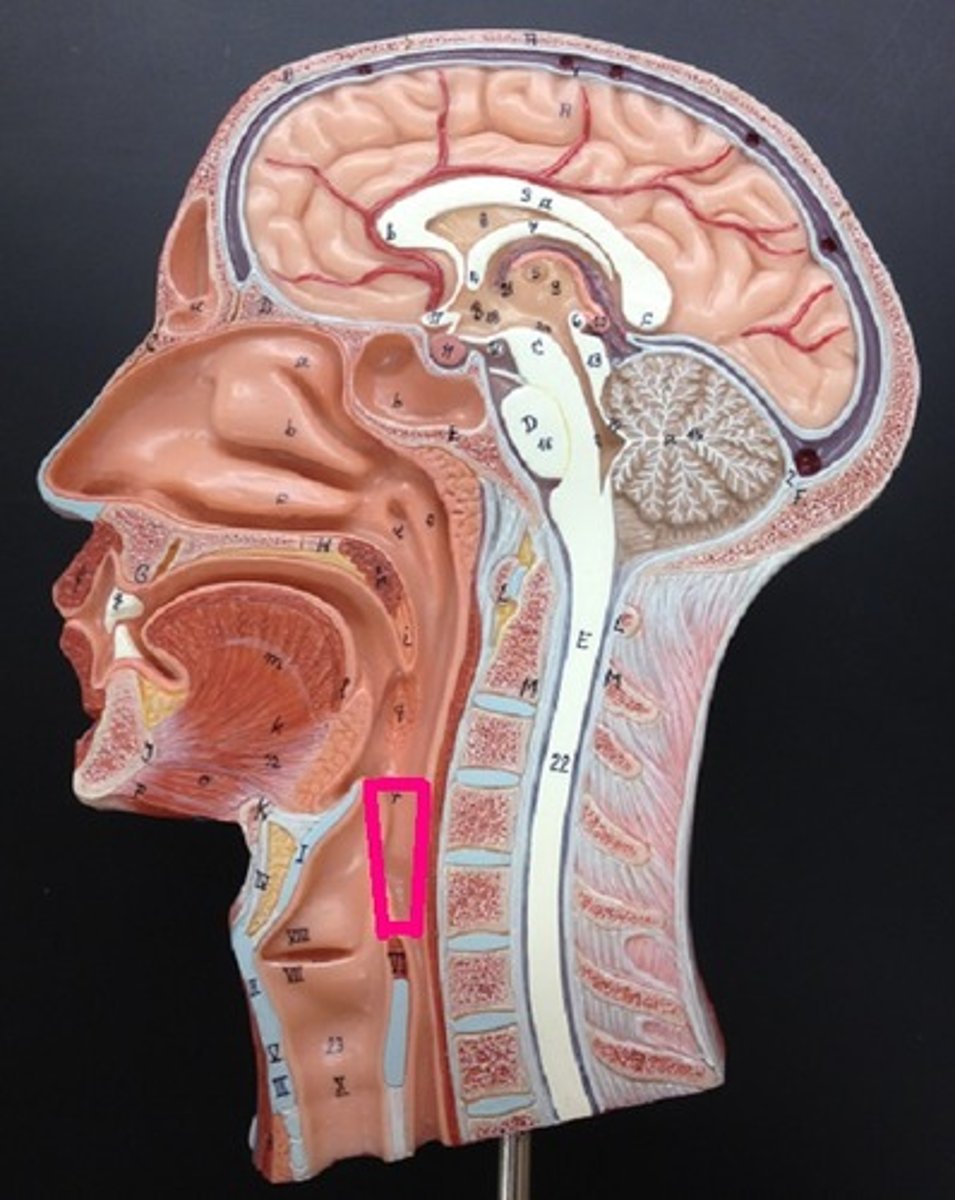

Pharynx

The membrane-lined cavity behind the nose and mouth, connecting them to the esophagus.

Nasopharynx

Oropharynx

Laryngopharynx

Larynx

Trachea

Sternocleidomastoid

Located at the base of your skull on either side of your neck, behind your ears. On both sides of your neck, each muscle runs down the front of your neck and splits to attach to the top of your sternum and collarbone.